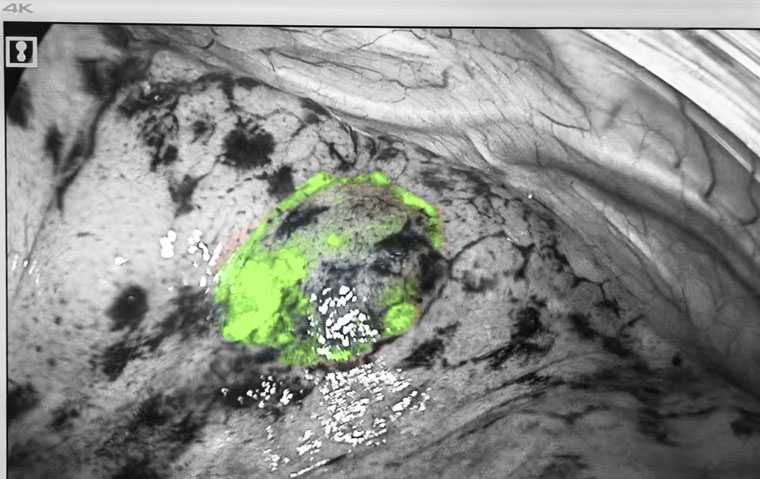

荧光显影标记

手术在麻醉三科贾丽主任团队全程保障及东院手术室护理团队的协助下进行。黄超主治医师操作电磁导航支气管镜,胸科内镜室张金泽技师长、边媛媛主管护师全力配合。患者全麻后,医疗团队经气管插管进镜,在电磁导航的实时指引下分别到达两处病灶位置,并将荧光显影剂通过内镜鞘管分别滴注至两处病灶定位标记,整体操作时间仅10余分钟。定位后,胸腔镜手术随即进行。荧光模式下,在肺表面即可看到定位的荧光显影标记,术者对病灶进行精准切除。术中快速冰冻病理显示,右肺上叶前段楔形考虑微浸润性腺癌,肺上叶后段楔形肺组织内可见纤维化结节,周边局灶肺泡上皮非典型增生,最终石蜡病理回报吻合口切缘阴性,表示边缘未发现肿瘤细胞,手术已完整切除病变。